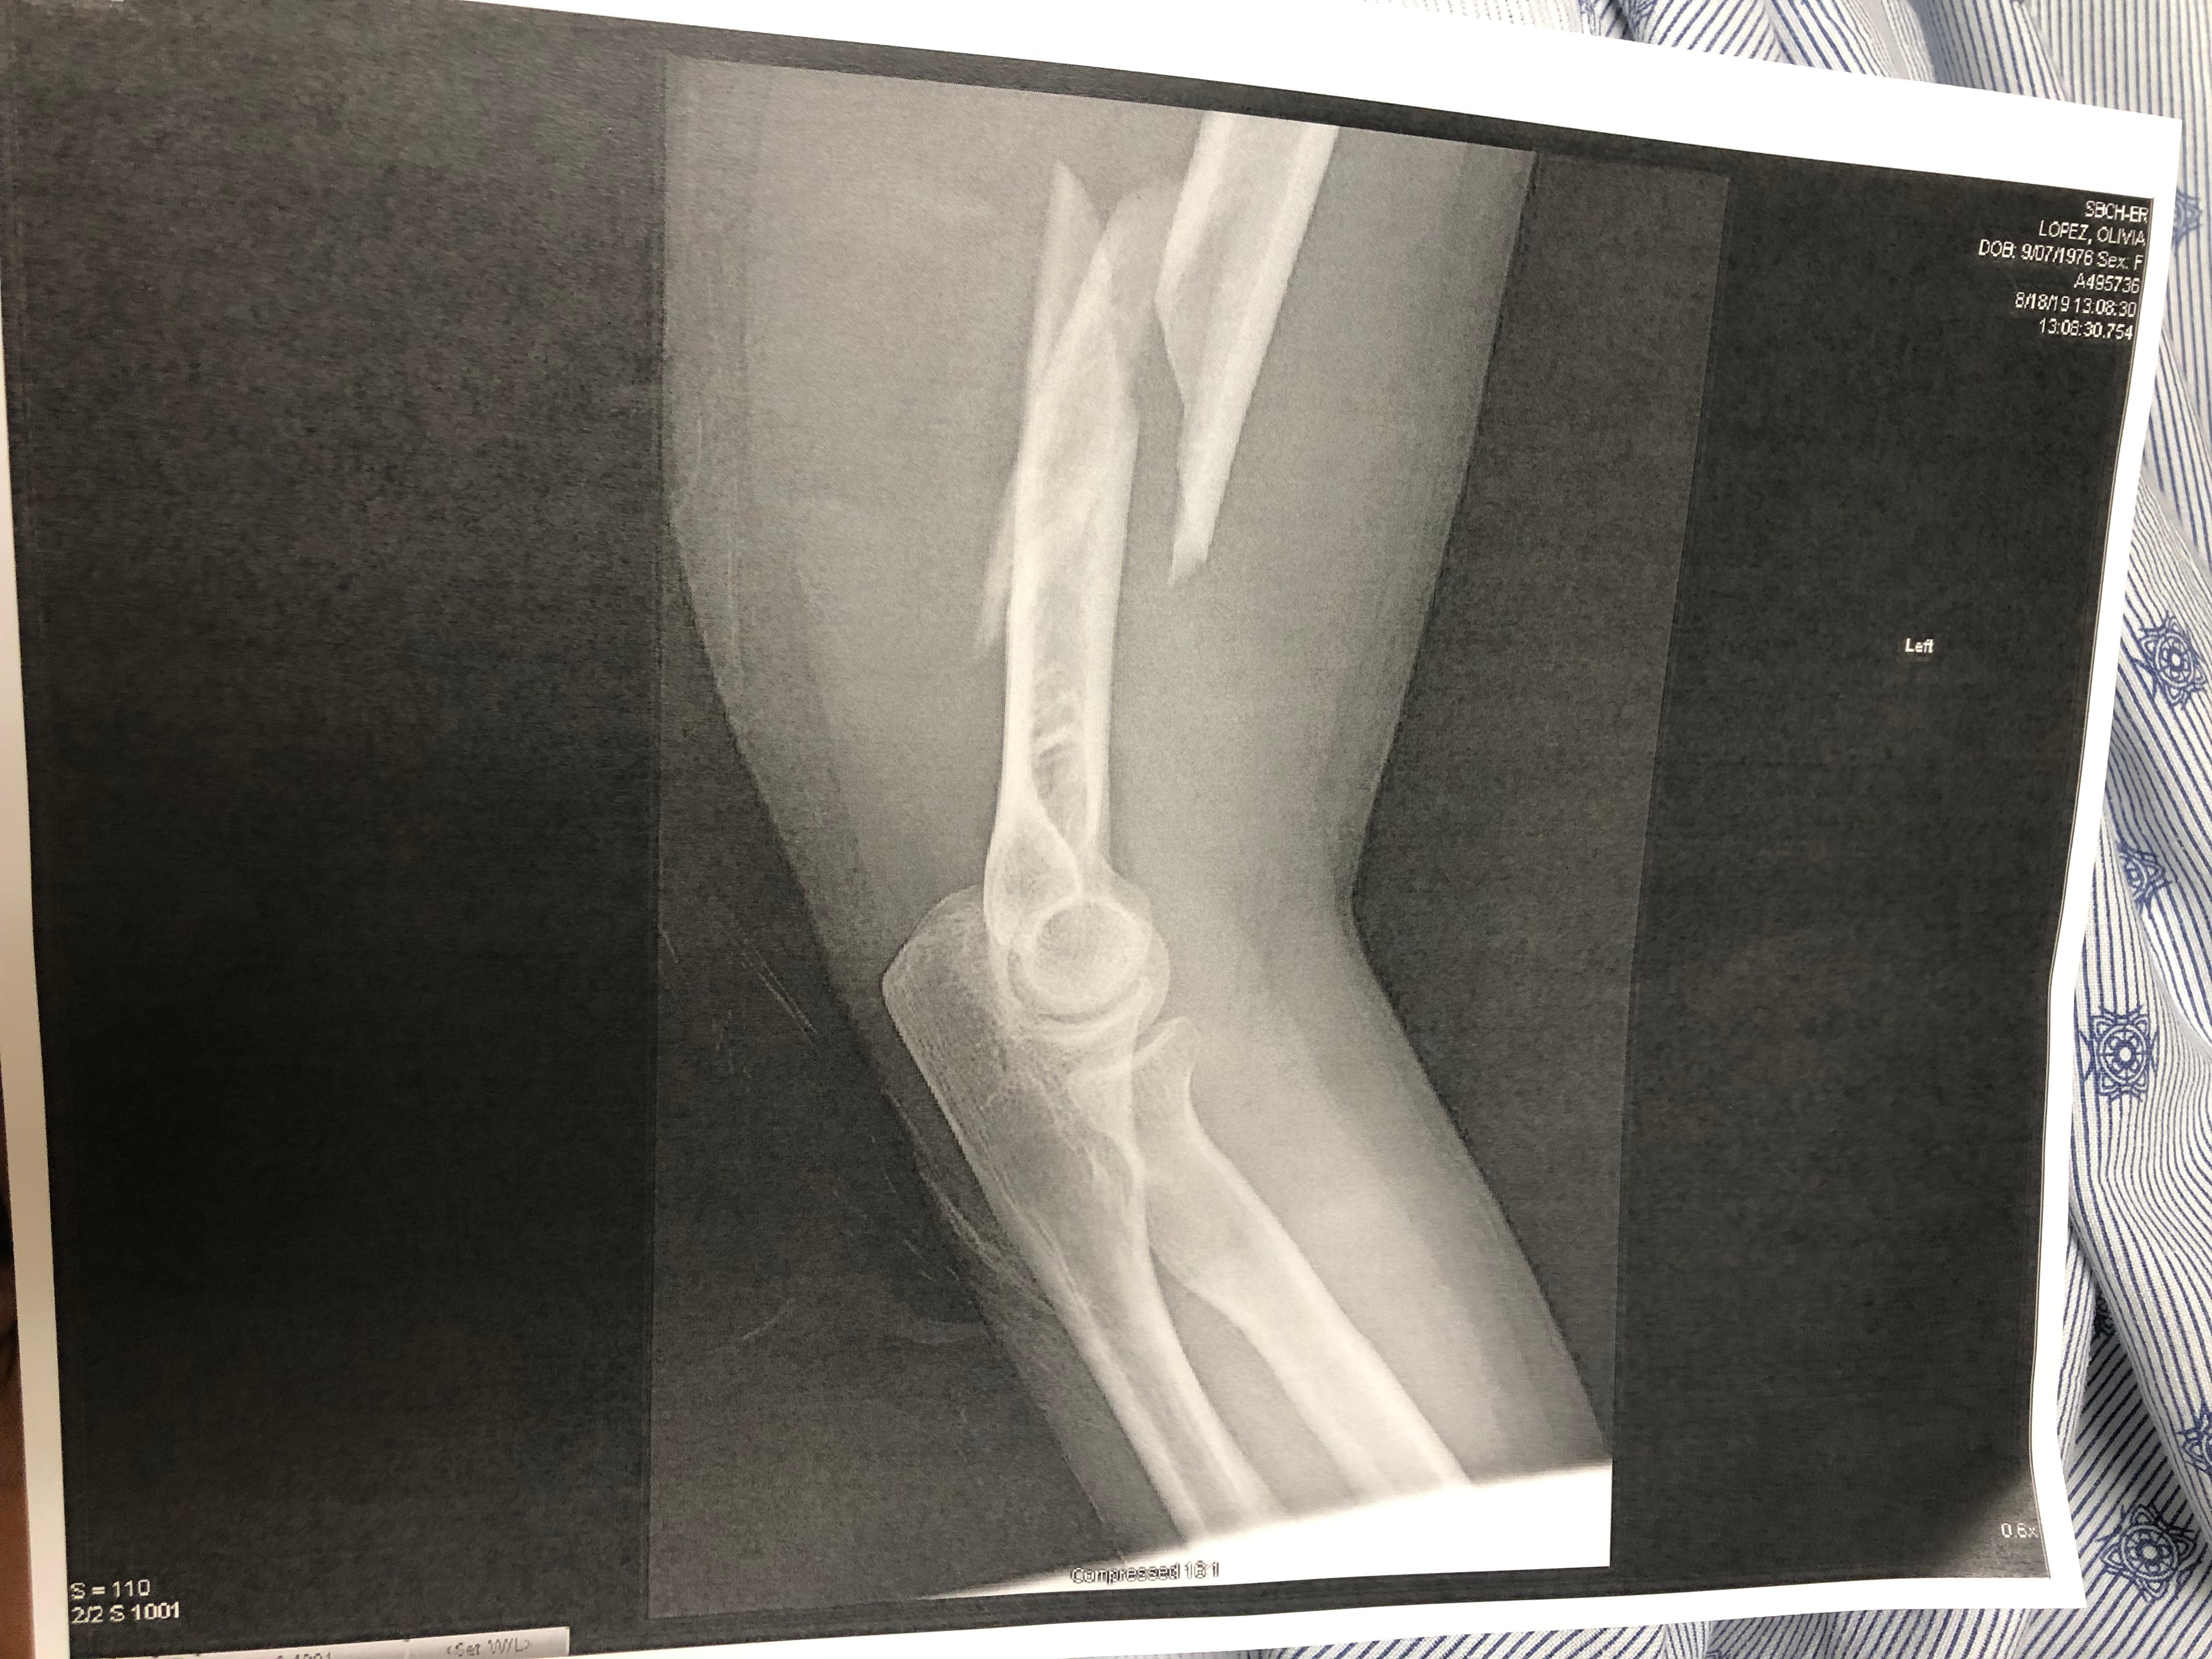

Rapp immediately releases Lopez’s arm and maintains a loose grip on the back of her neck as he calls for an ambulance. Lopez stands still and continues to sob. She is transported to Cottage Hospital, where an x-ray reveals her left humerus has sustained a spiral fracture, which occurs when an extreme amount of torque is applied along the axis of a bone. During a subsequent interview with a Spanish-speaking investigating officer at the hospital, Lopez asks if he is “a real policeman” or if they are in “some kind of TV show.” “Many of her statements were nonsensical,” the report says.